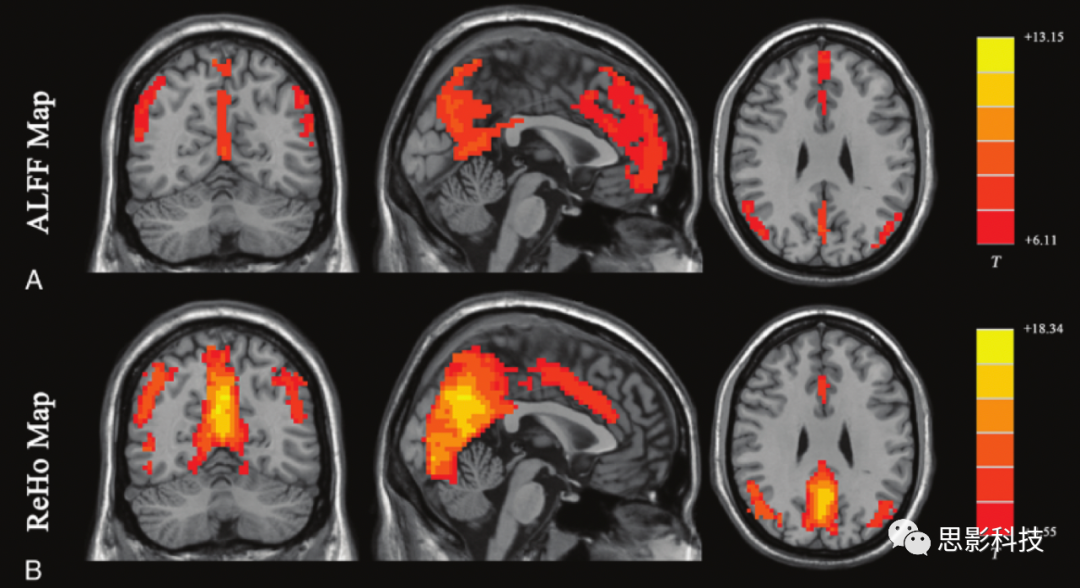

在靜息態(tài)功能磁共振研究中,具有較好的可重復(fù)性和較為明確生理意義的指標(biāo)主要有兩種,分別是低頻振蕩振幅(ALFF)和局部一致性(regional homogeneity, ReHo)。它們反映的是局部腦活動(dòng)(城市”),不顯示不同腦區(qū)之間的功能連接(高速路”)。盡管兩種分析結(jié)果有很多相似之處,但反映的內(nèi)容是不同的,兩種方法相結(jié)合可得到更多的信息。

200例健康志愿者ALFFReHo分析結(jié)果。

ALFFReHo的分析結(jié)果均可用于反映大腦的局部神經(jīng)活動(dòng)特征,異常腦區(qū)可作為ROI進(jìn)行下一步的功能連接分析。